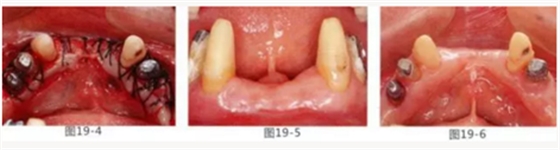

圖19-3 左下3,4,5部位進行FGG(游離齦移植)去除牙周袋以及獲得附著齦。同時進行骨外科處理。相反側(cè)也進行同樣的處理。

圖19-4 將移植片固定于右下3,4左下3,4,5的舌側(cè)骨膜,并進行牙周袋去除以及獲得附著齦。

圖19-5,6 術(shù)后1個月唇舌側(cè)的愈合狀態(tài)。唇舌側(cè)都獲得了足夠附著齦。